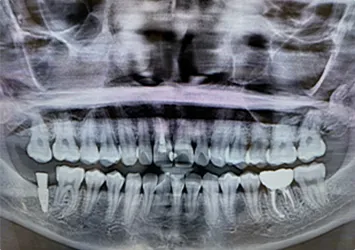

治療前

治療前写真 恵比寿南DENTAL 治療前写真 恵比寿南DENTAL

治療後

治療後写真 恵比寿南DENTAL 治療後写真 恵比寿南DENTAL

施術内容

【20代女性】

右下7番の歯根破折してしまい保存不可能となってしまった歯を抜歯し、インプラント埋入

治療期間

5ヶ月

リスク

術中の不可抗力によるトラブル(出血など)、術後注意事項を守らないことによる疼痛、感染、上部構造装着後口腔内清掃を怠ったことによるインプラント周囲組織の炎症

副作用

治療後の口腔内清掃、及びメインテナンスを怠ったことによるインプラント周囲粘膜炎またはインプラント周囲炎

費用

インプラント埋入:30万円

ジルコニアクラウン:12万円